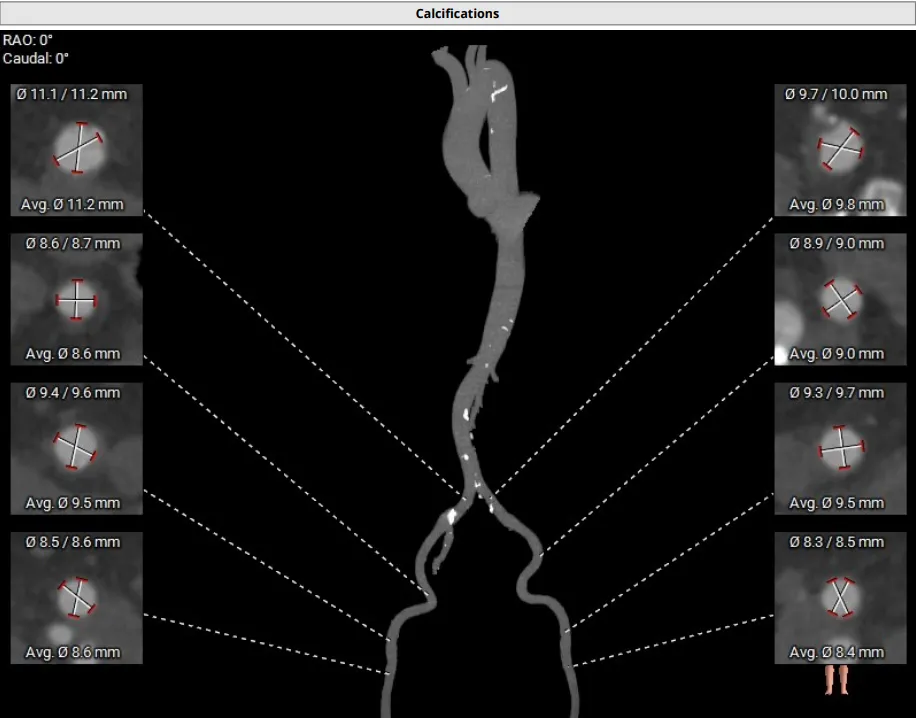

主动脉瓣术前CTA评估

收缩期瓣环直径

27.7mm

收缩期LVOT 2mm

直径 27.8mm

收缩期LVOT 4mm

直径 28.5mm

收缩期LVOT 6mm

直径 29.5mm

SOV:39.6mm

SOV:36.8*35.0*39.2mm

瓣环平面夹角:46°

瓣下MS:2.5mm

左侧冠脉开口高度20.0mm

右侧冠脉开口高度21.2mm

外周入路情况良好

右侧股动脉分叉位置可

左侧股动脉分叉位置偏高